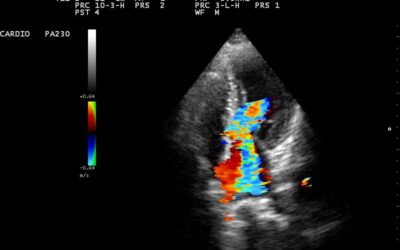

- Ecografie cardiaca bidimensionala si Doppler

Cardiomiopatie hipertrofica

Coarctatia